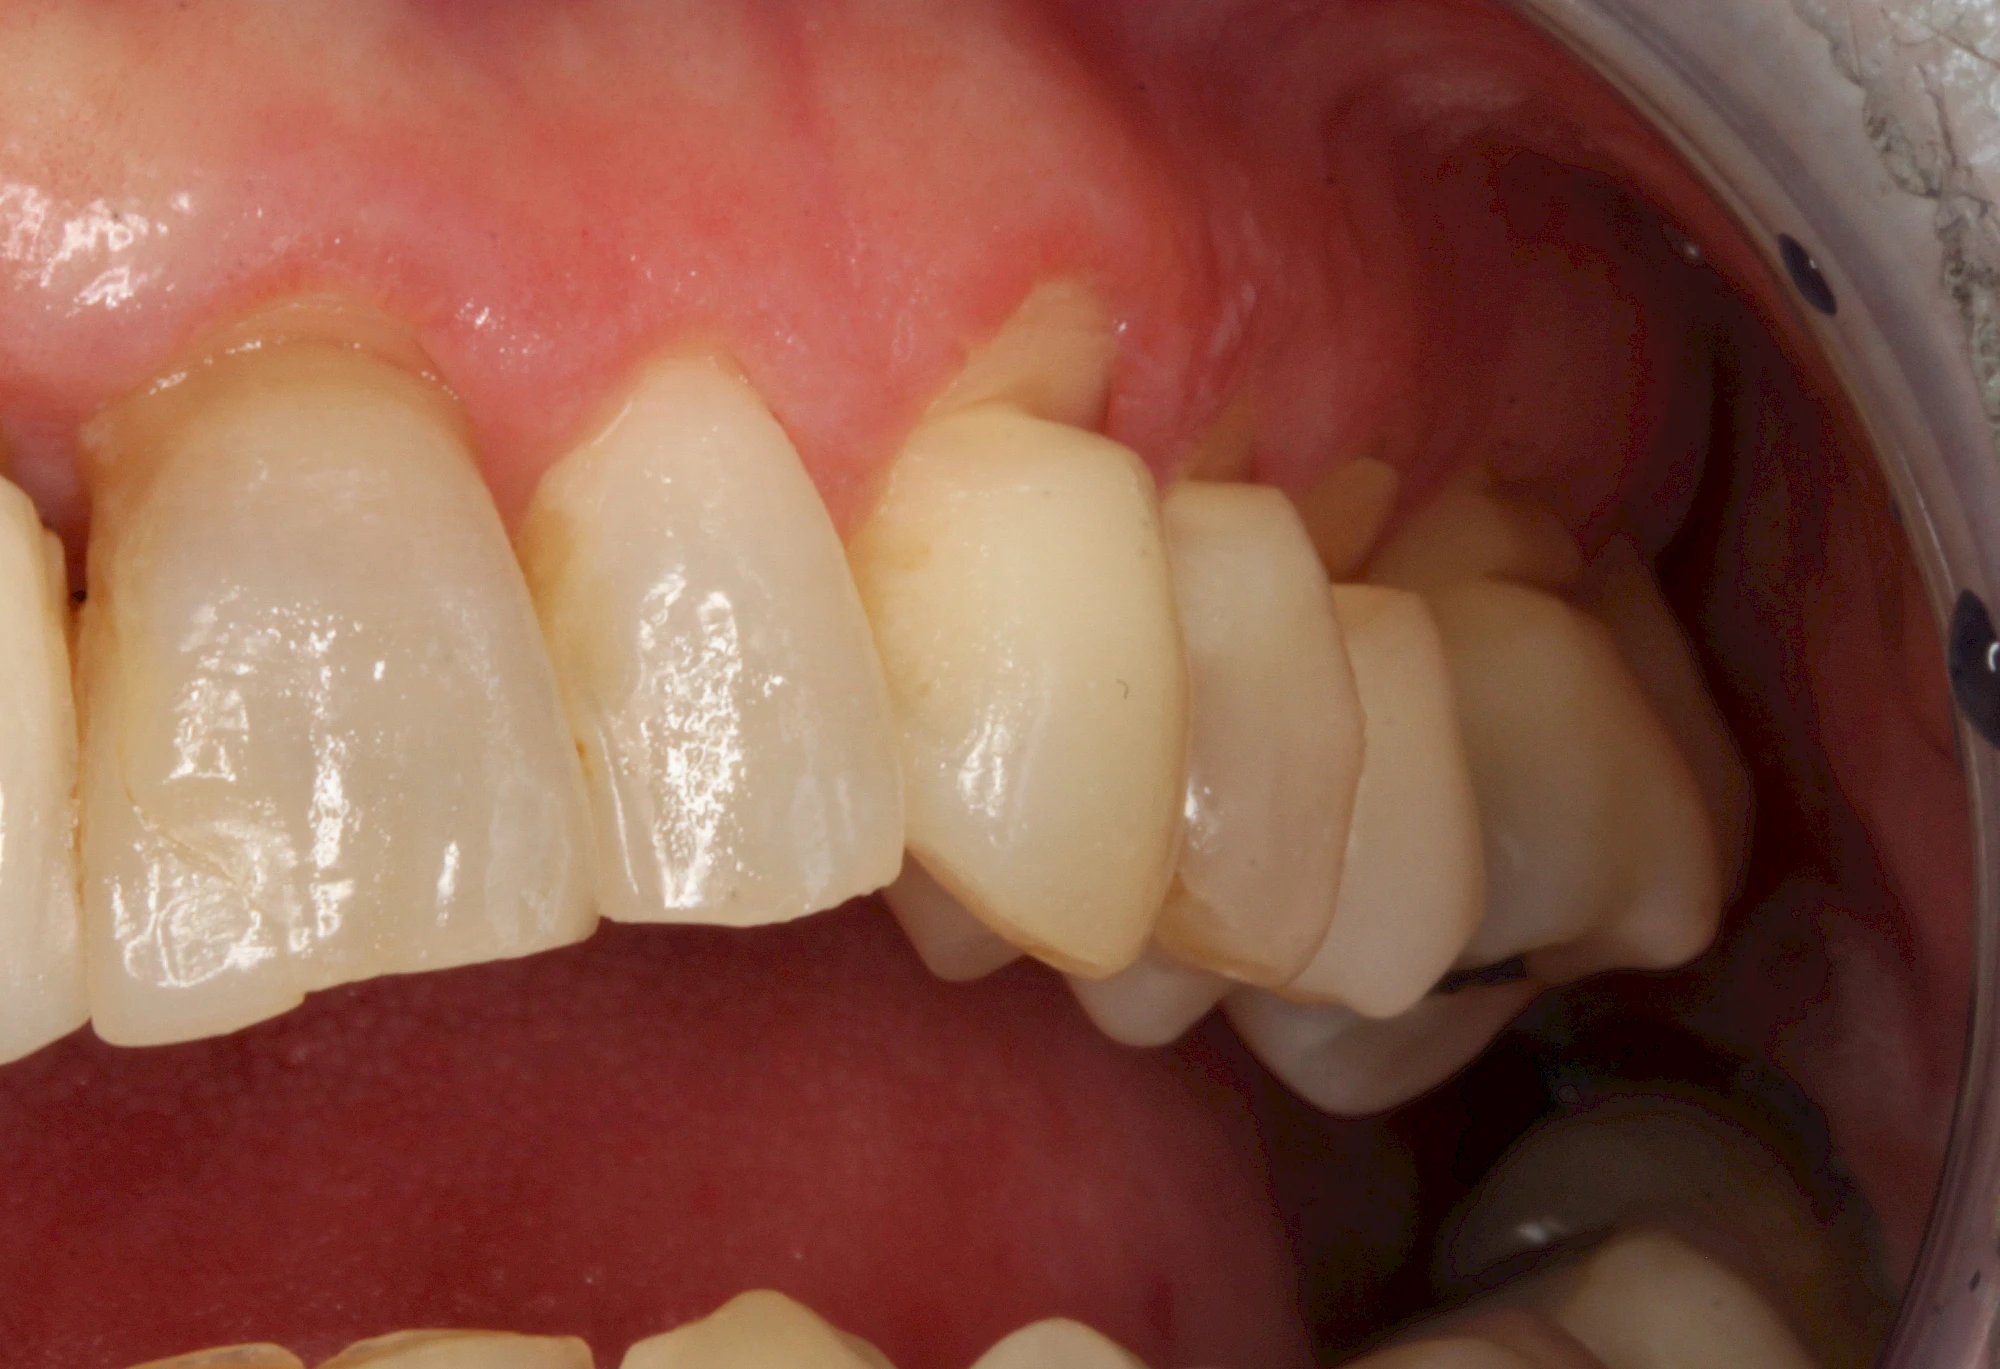

Keilförmiger Defekt

Eine Sonderform sind sogenannte keilförmige Defekte im Bereich der Zahnhälse. Hier geht man davon aus, dass Knirschen und Pressen in Kombination mit falschen Putzgewohnheiten (zu hoher Putzdruck, Verwendung von Zahnpasta mit hohen Abrasionswerten) eine Rolle spielen.